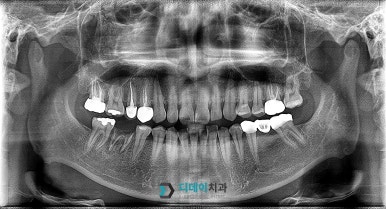

<전 2022-03-24>

<후 2022-07-01>